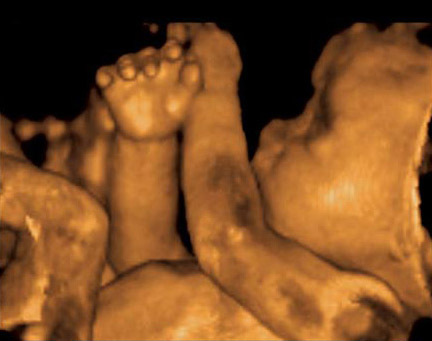

Las ecografías 3D y 4D pueden realizarse en cualquier momento del embarazo aunque las mejores imágenes se obtienen entre las semanas 24 y 30 pues las condiciones son las más adecuadas. La proporción de líquido amniótico y el tamaño intermedio del bebé permiten visualizarlo mejor.

A partir de la semana 12 y hasta aproximadamente la 20 se puede ver al feto en su totalidad viendo tronco y extremidades al mismo tiempo, pero no se podrán ver tan en detalle las facciones de la carita.

En cambio, al realizarla hacia fines del segundo trimestre o principios del tercero (alrededor del 6to o 7mo mes) no lo veremos completo, sino en partes pero obtendremos imágenes más reales del bebé pues sus rasgos estarán ya más definidos y podremos verlo, por ejemplo, haciendo muecas, chupándose el dedo o sacando la lengua.

A medida que avanza el tercer trimestre el bebé ya tiene un aspecto muy similar al que tendrá cuando nazca, pero después de la semana 32 su tamaño, la posición y una menor proporción de líquido amniótico puede dificultar que podamos ver al bebé de forma nítida o que no podamos verle bien la carita.